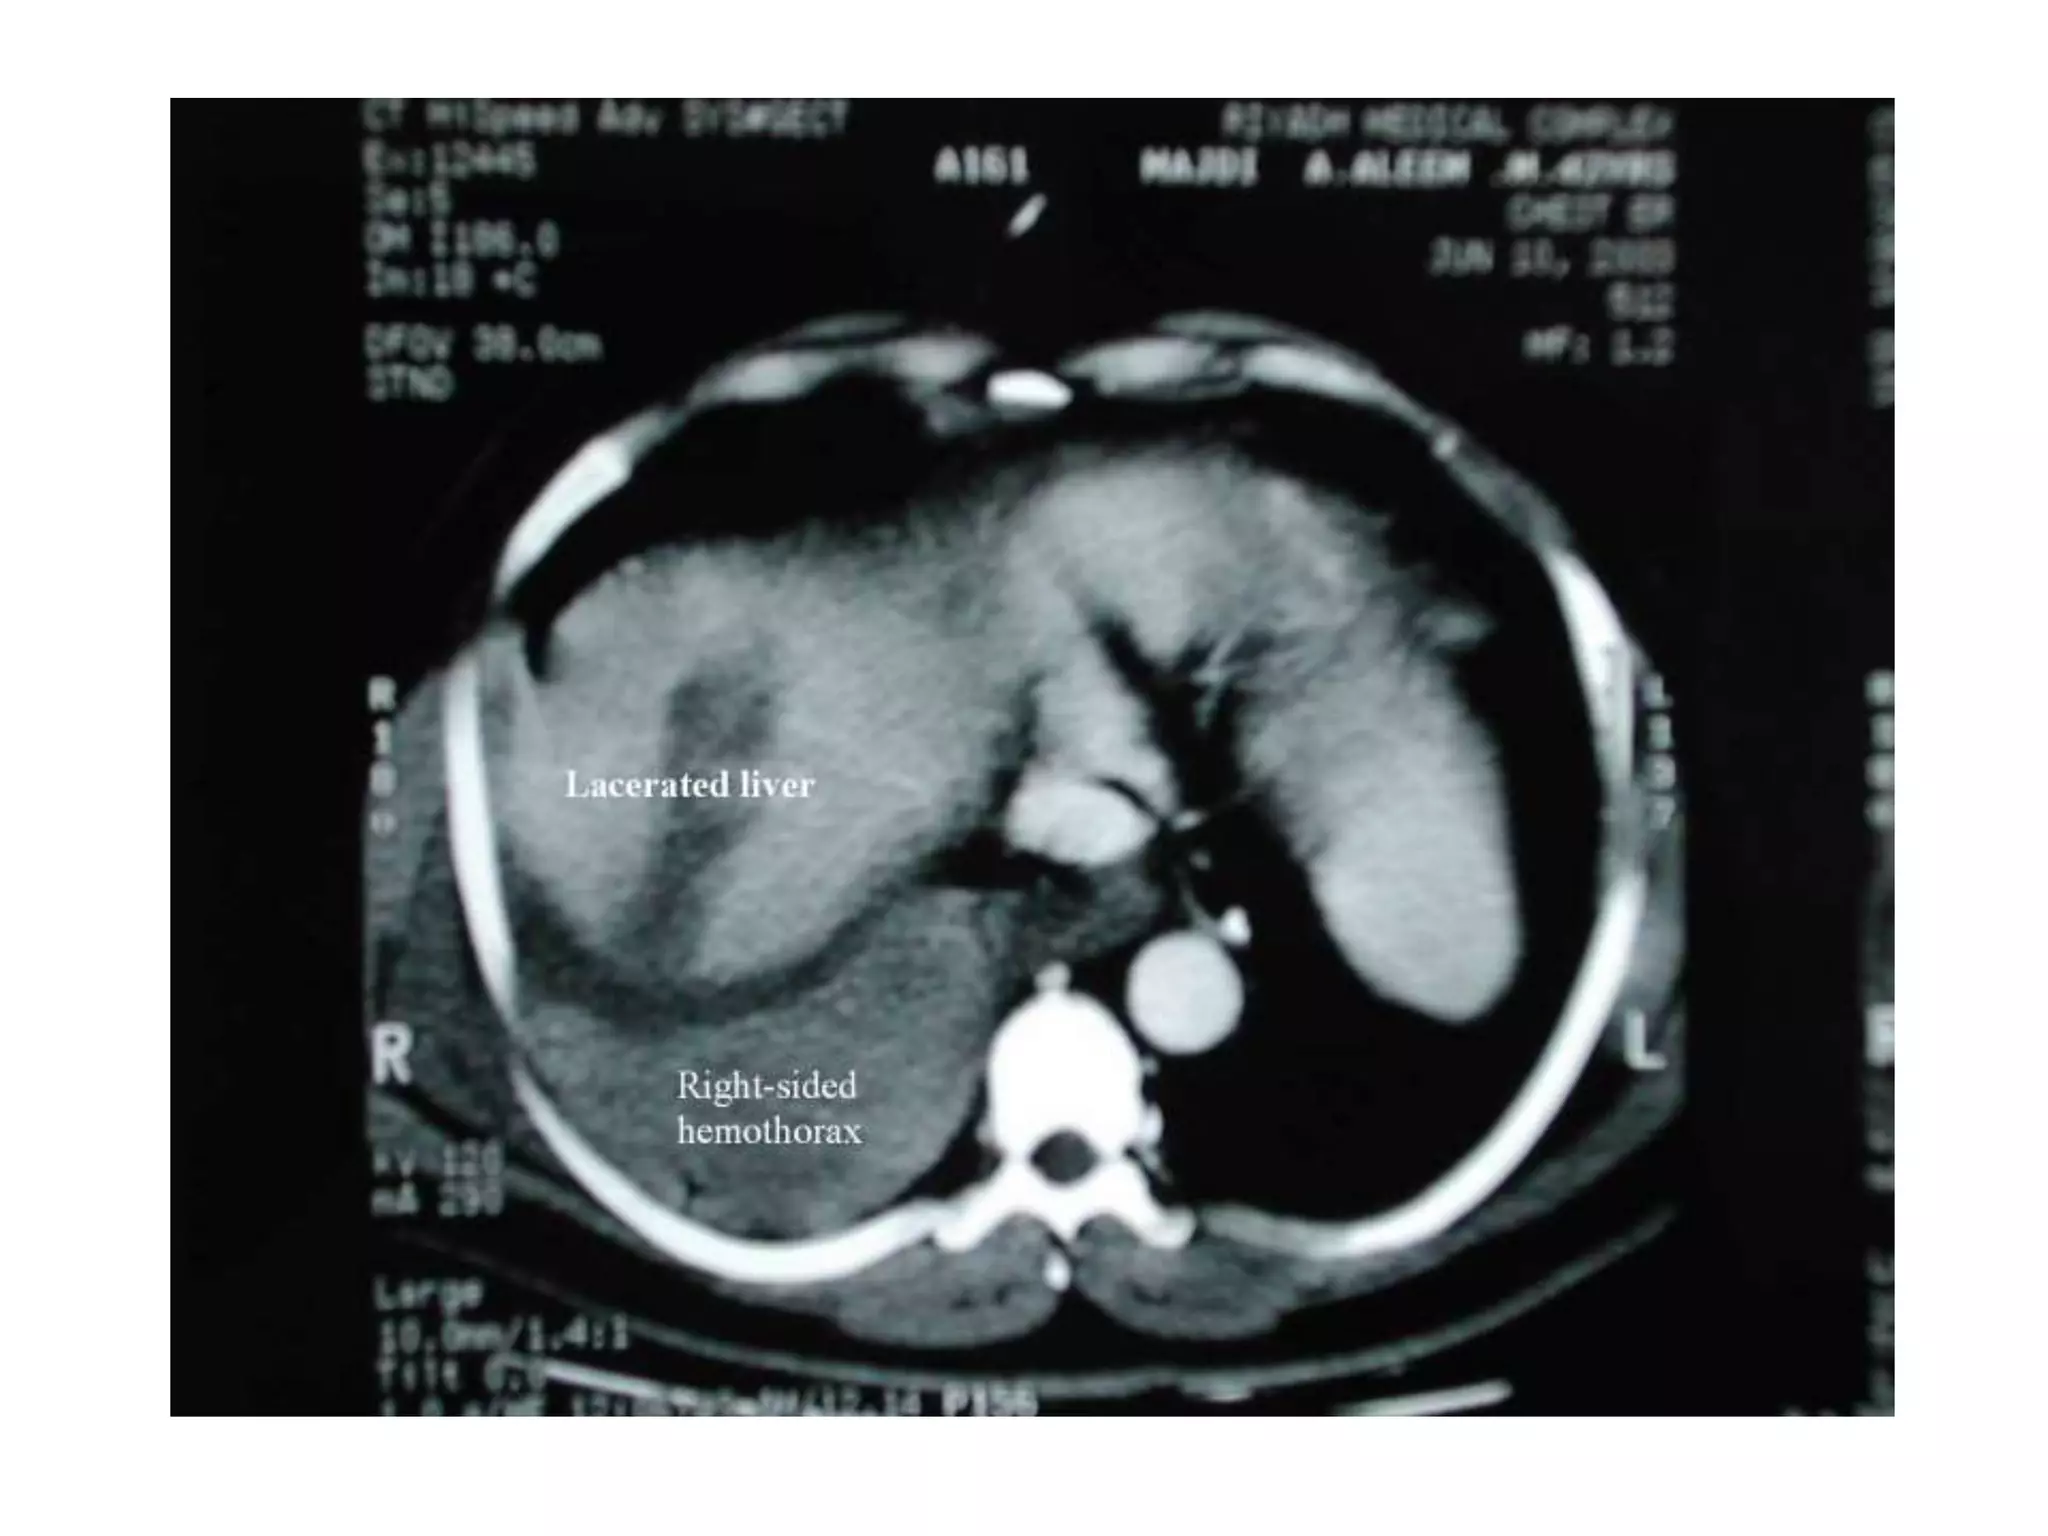

(b) CT.Scan abdomen

used for diagnosing

intraperitoneal injuries in

stable patients after blunt

trauma.